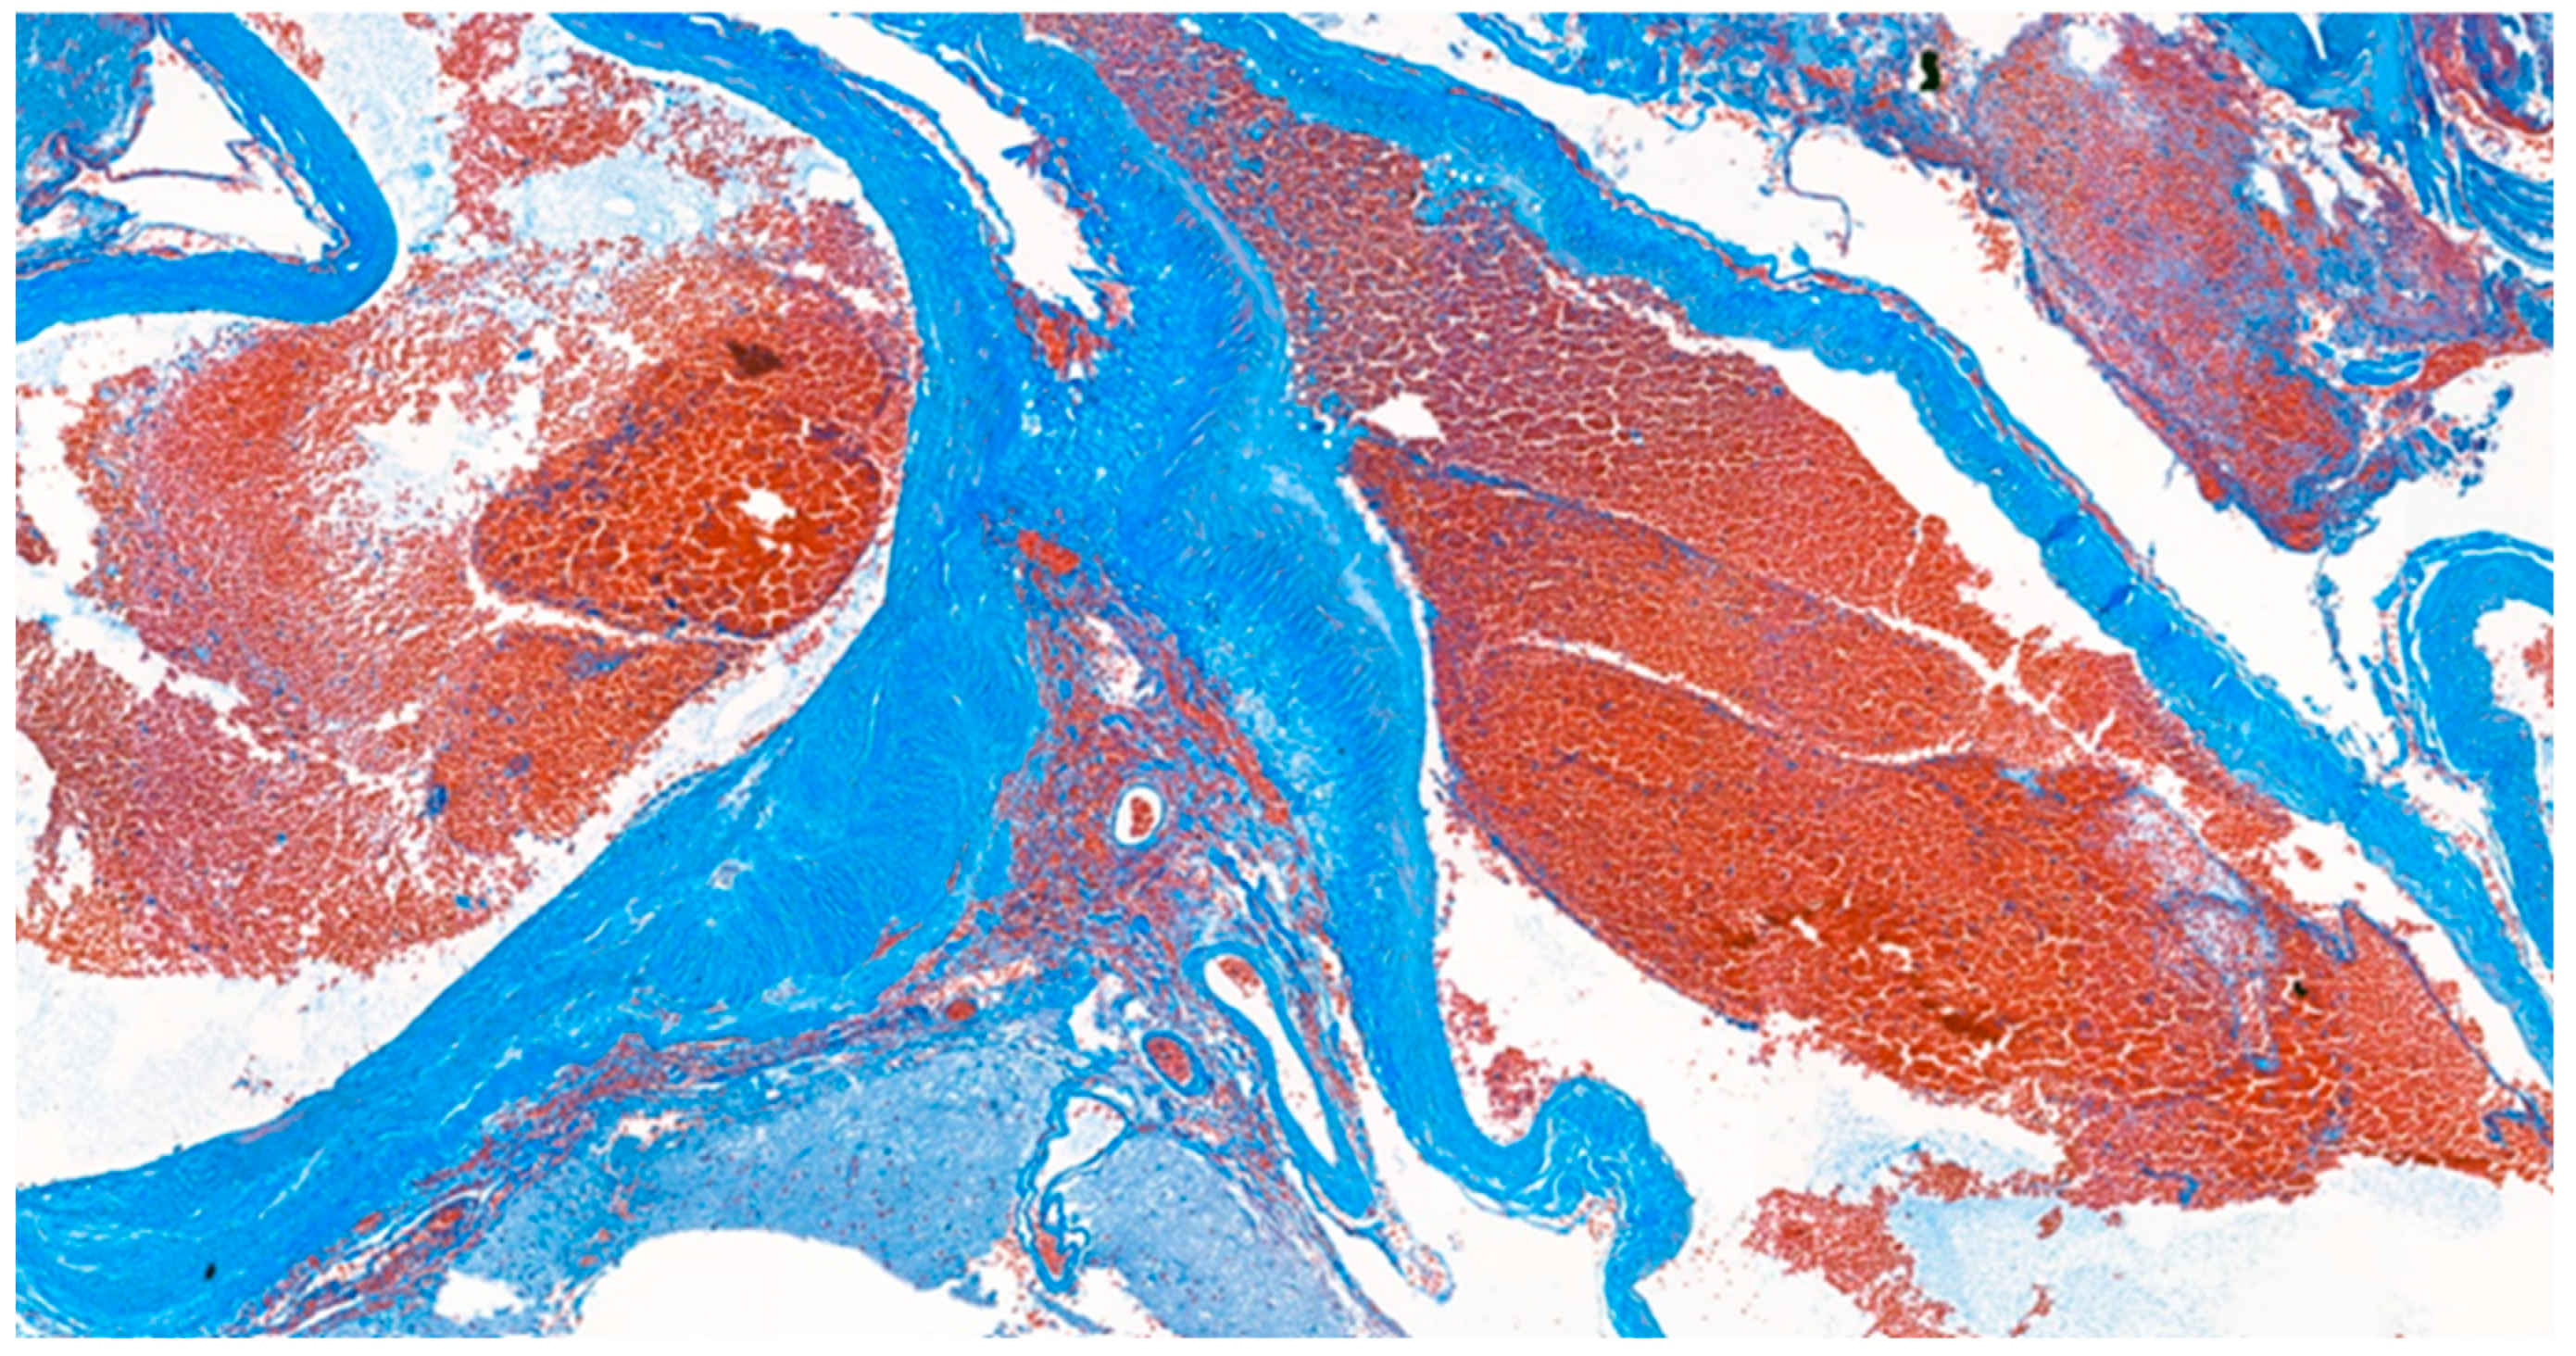

Histopathological analysis of the tumor revealed glioblastoma (WHO grade IV), with increased cellularity, cellular atypia, and frequent mitotic figures. Glomeruloid microvascular proliferation and tumor necrosis were also found Figure 4 and Figure 5. Immunohistochemical (IHC) staining revealed a positive stain of glial fibrillary acidic protein (GFAP), isocitrate dehydrogenase-1 (IDH-1) and alpha thalassemia/intellectual disability X-linked gene (ATRX) Figure 6A–C. A wild-type pattern presentation of p53 protein was also noted Figure 6D. In addition, the other specimen revealed a mixture of abnormally muscularized arteries without continuity and a complete three-layer structure under Masson’s trichrome stain Figure 7. Furthermore, ambiguous vessels exhibiting both artery and vein characteristics that were compatible with AVM under Verhoeff–Van Gieson stain Figure 8.

Figure 7.

Masson’s trichrome stain. The histological stain revealed abnormally muscularized arteries.